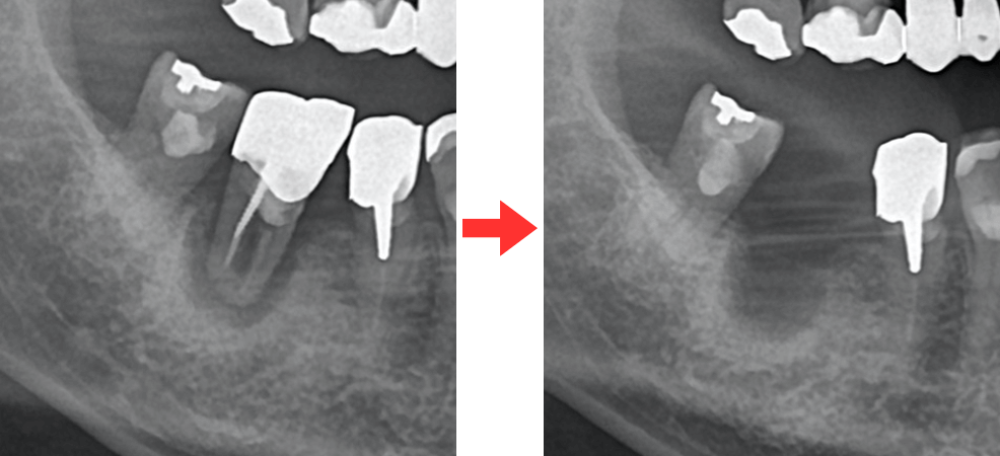

↑歯の根の病気が原因(根尖性歯周炎)で、歯を喪失。抜歯4ヶ月後のレントゲン画像。骨はほとんど回復していない。

このように、歯が存在することで顎の骨(歯槽骨)が保たれています。

歯を失うと、その部分の骨は 自然に痩せていく のです。